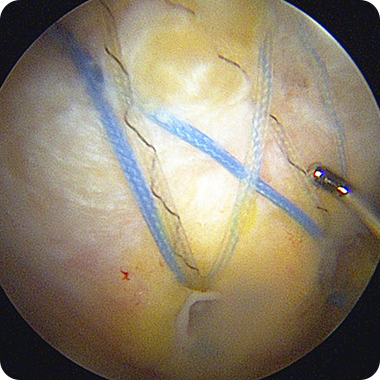

봉합 상태를 내시경으로 확인한 뒤

절개 부위를 봉합하고

수술을 마무리합니다.